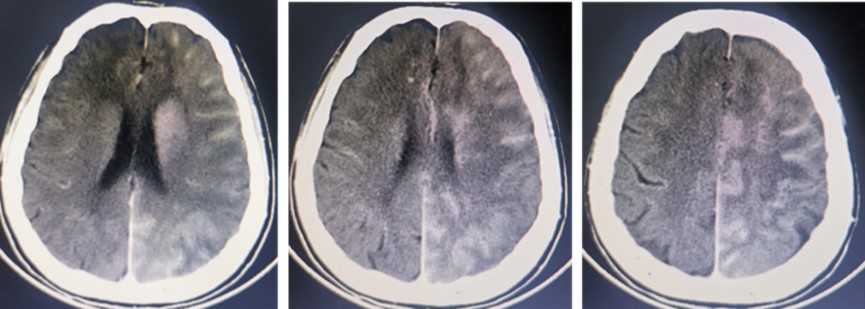

我们立即陪同患者完善颅脑CT检查,显示左侧大脑半球广泛散在高密度影,没有明显的占位效应,考虑为造影剂外渗所致,不存在与临床症状匹配的血肿(图3)。

图3 术后颅脑CT显示左侧脑内及脑沟脑裂多发斑高密度影,提示造影剂渗漏